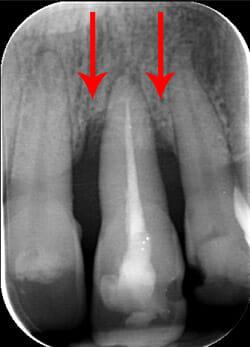

Endorale prima e dopo la cura della parodontite

Con terapia parodontale microinvasiva: si noti la ricrescita naturale dell’osso e del tessuto parodontale.